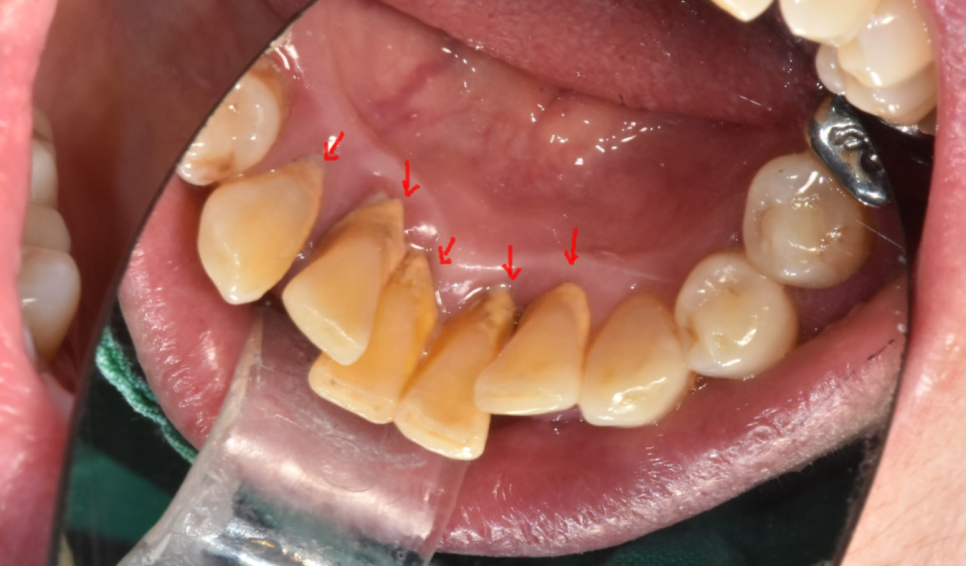

사진을 보시면 아래 앞니 1개가 솟구쳐 올라와있죠?

다른 치아에 비해 키가 유독 큰 모습입니다.

치아가 솟구쳐서 불편해요

깎아주세요

“요즘 자꾸 윗니랑 부딪혀서 불편해요”,

“치아를 조금만 깎아주세요” 하고 오시는 경우가 많습니다.

하지만 이건 치아가 자라는 게 아닙니다.

치아가 길어진 게 아니라,

잇몸뼈가 녹아내린 겁니다

치아가 길어보이는게 알고보면...

잇몸이 내려가면서 뿌리 부분까지 노출되어 길어져 보이는 것일뿐

실제 치아 길이가 길어진 것은 아닌데요.

240517 붙어있는 치석들